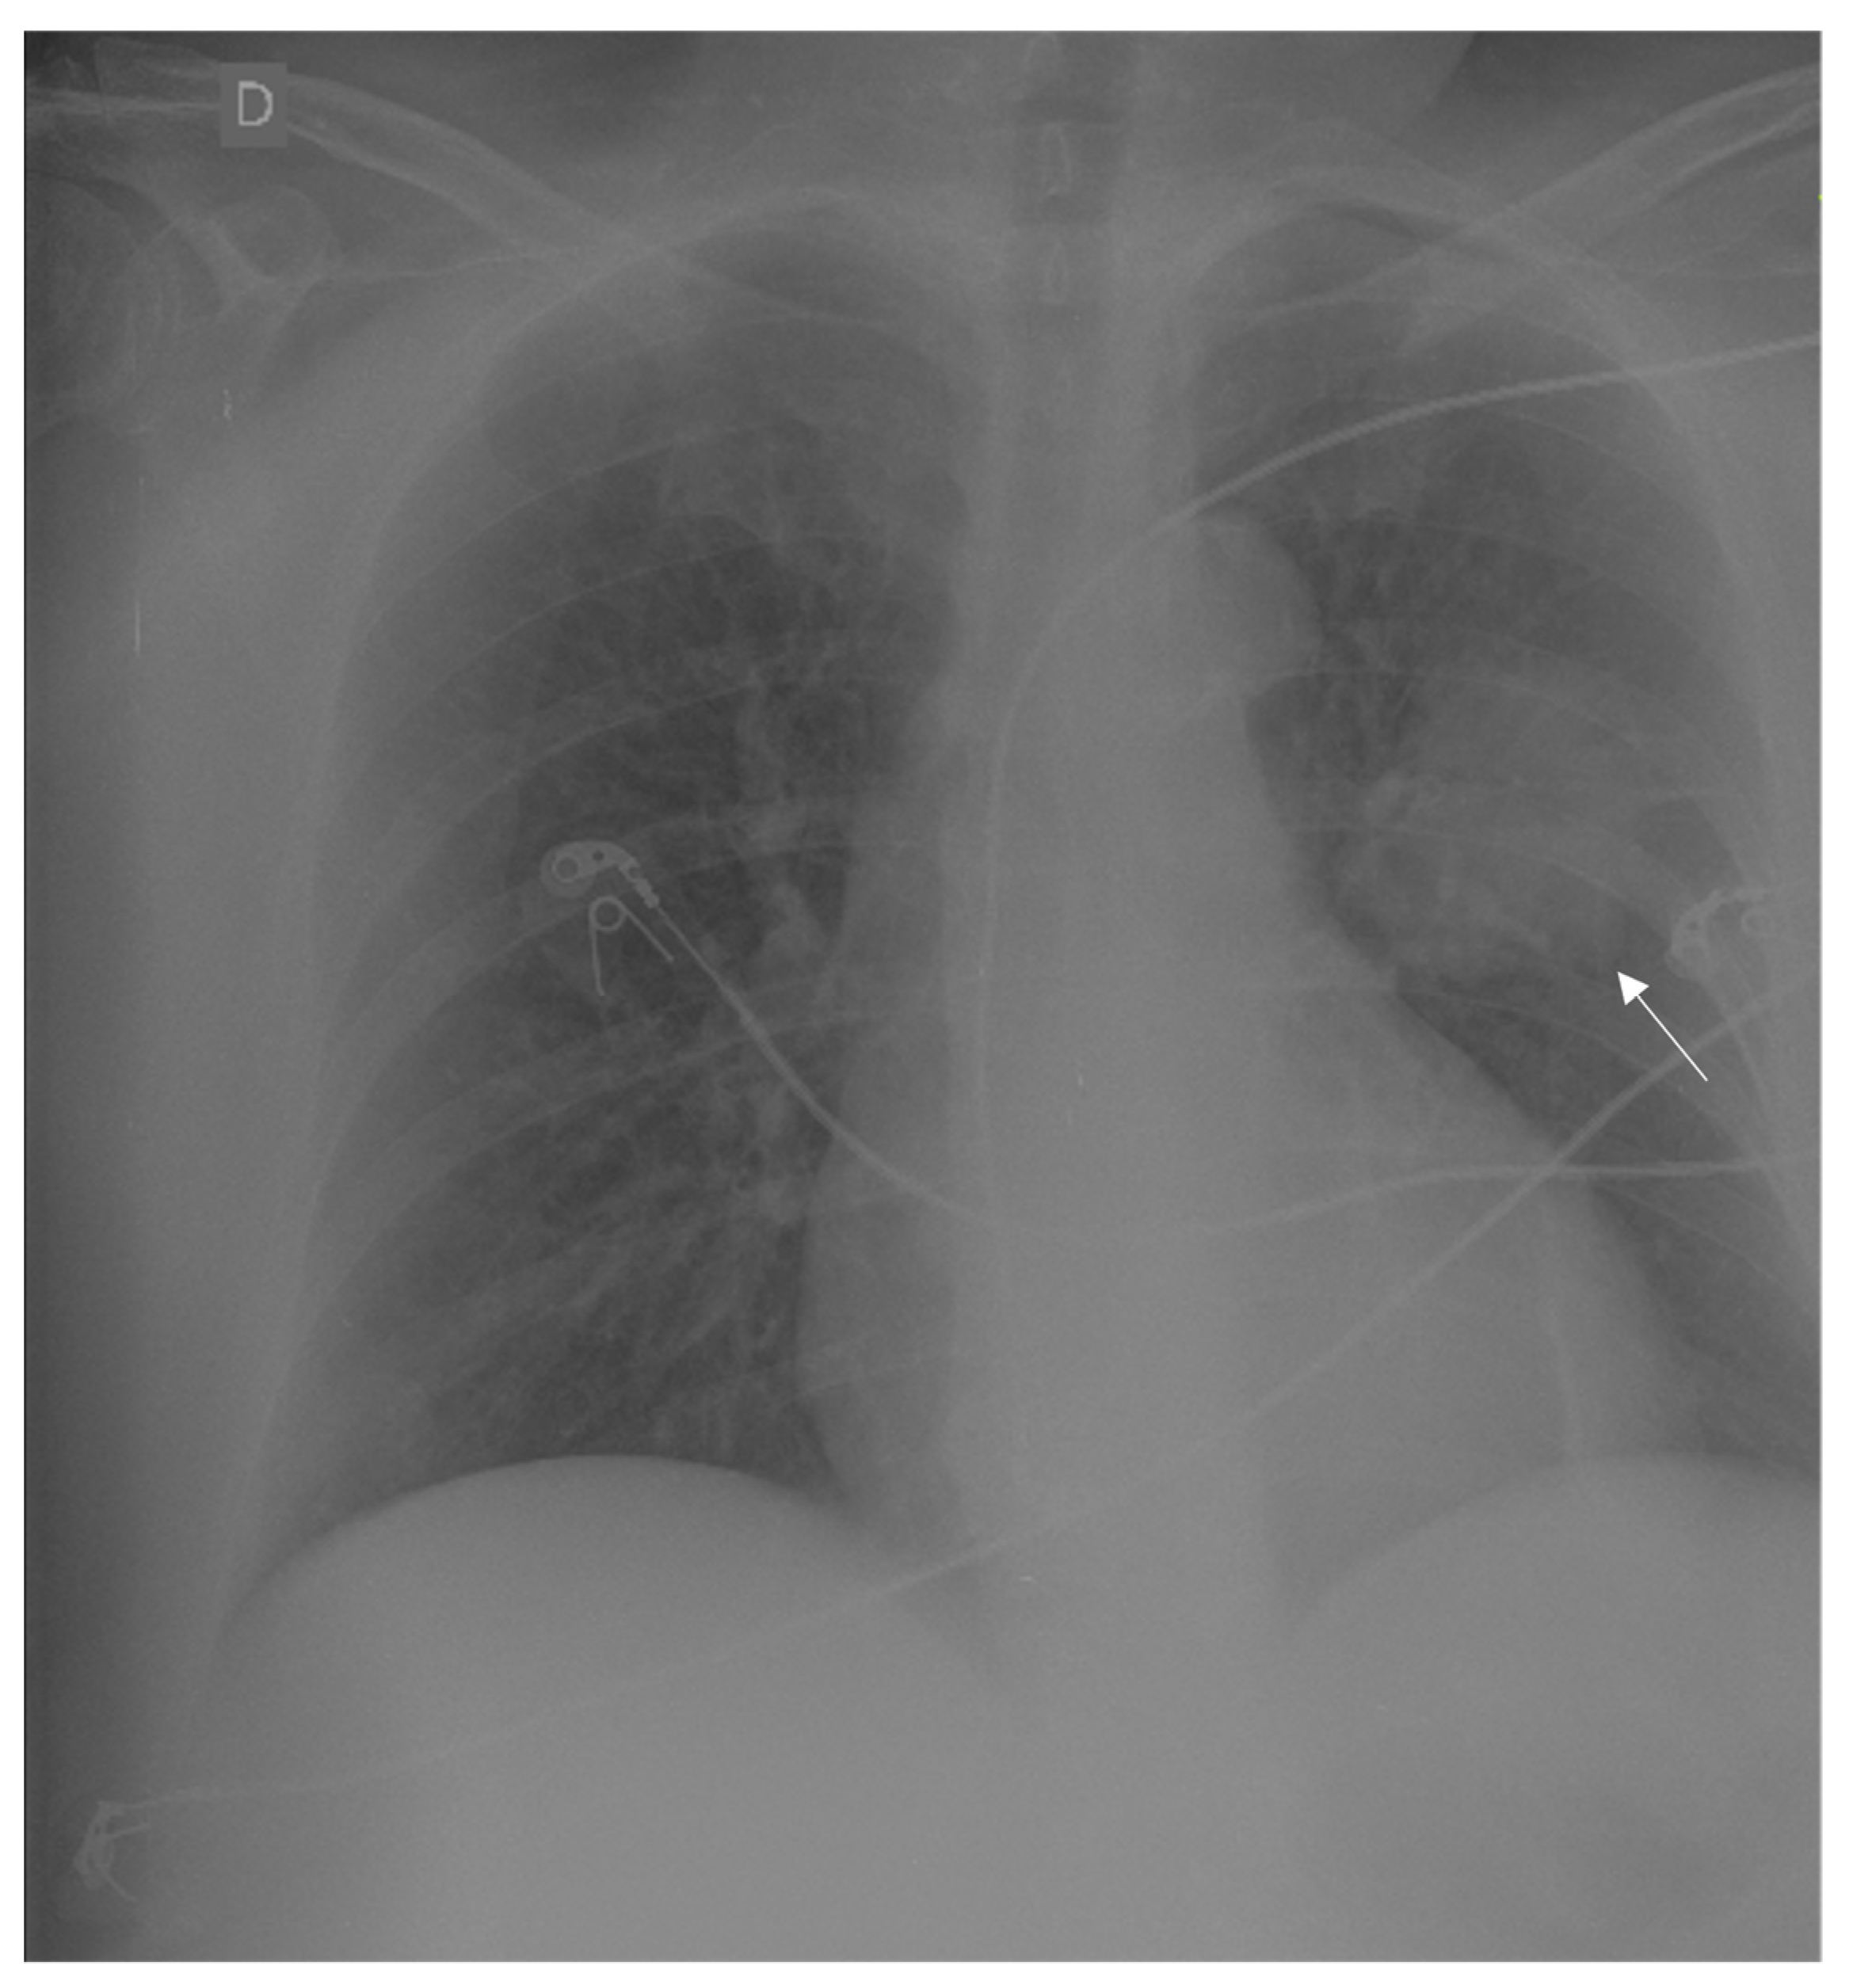

2. Case Report